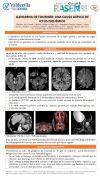

Angiosarcoma cerebral multifocal. Un desafío diagnóstico multidisciplinar. A propósito de un caso